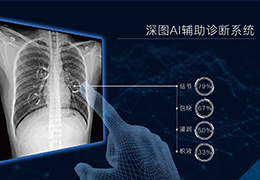

分析智能。

这些功能利用数字控制面板分析运营、业务和临床绩效。

使管理员能够跟踪关键参数,包括平均曝光率、拒绝的影像和探测器统计信息。

帮助确定需要改进的方面,支持为员工和部门制定适当的改进计划。